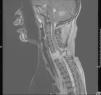

Niña de 5 años que sufre un accidente de tráfico por impacto frontal, con signos de traumatismo externo abdominal y un nivel de conciencia fluctuante, con ventilación espontánea, sin reacción a estímulos dolorosos, con pupilas isocóricas normorreactivas, frecuencia cardiaca 85lpm, presión arterial sistólica 90–95mmHg. De forma brusca, presenta deterioro hemodinámico, con disminución de frecuencia cardiaca, aleteo nasal y respiración bucal, siendo intubada, con GCS 3, en situación de shock (fig. 1). En ecografía abdominal se observa abundante cantidad de líquido libre, requiriendo resección quirúrgica urgente de 2 segmentos de intestino delgado por perforación y desgarro del meso. Una vez estabilizada, se realiza TC cerebral y de columna cervical, objetivando infarto cerebeloso izquierdo y fractura-distracción de C7, con invasión de canal. Ante la sospecha de lesión medular se realiza una RM de columna cervical (fig. 2) con una fractura horizontal de la porción inferior de C7 con extensión y separación de elementos posteriores y pseudomeningocele. Se asociaba sección completa medular en la unión C7-D1, con disección de la arteria vertebral izquierda e infarto cerebeloso en territorio de la arteria cerebelosa posteroinferior izquierda (fig. 3). A las 48h, la paciente desarrolló un cuadro de distress respiratorio agudo y midriasis bilateral arreactiva, observando en TC cerebral un aumento del efecto masa del infarto cerebeloso e hidrocefalia triventricular, con herniación transtentorial, concluyendo con muerte encefálica confirmada en arteriografía cerebral.

DiagnósticoSección medular por fractura del cuerpo vertebral C7.